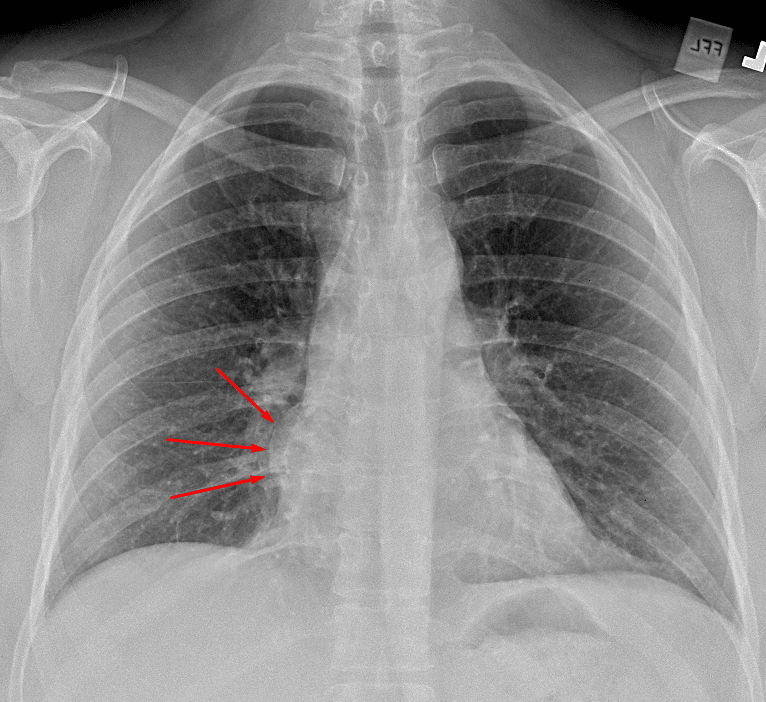

Approximately 4 cm mass in the mediastinum (red arrows) adjacent to the right heart border.